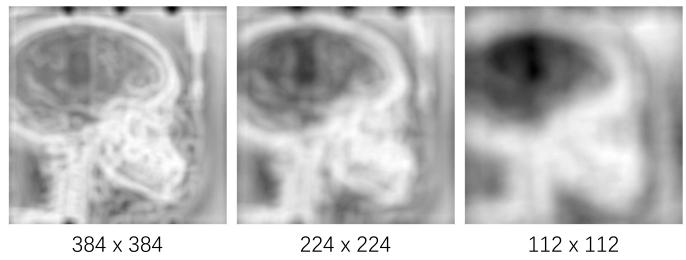

Fig. 5. Image information entropy maps of images with different sizes.

图 5 不同尺寸图像的图像信息熵图

Fig. 6. (left) Distribution of IIE of images with different resolutions. (right)Results of low-resolution images.

图6 不同分辨率图像的图像信息熵(IIE)相关结果 (左图)不同分辨率图像的图像信息熵(IIE)分布; (右图)低分辨率图像的实验结果。